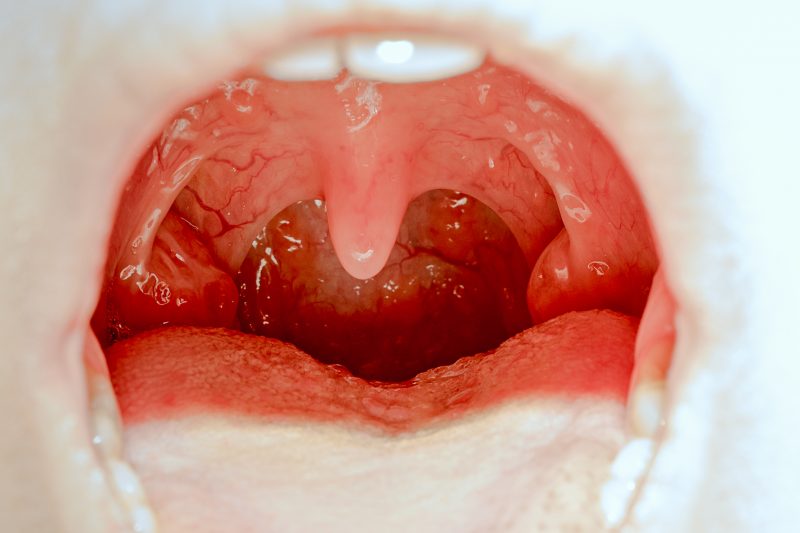

1) Non, les amygdales ne sont pas inutiles

Les amygdales, ce sont ces deux petites boules de chair situées à l’arrière de la bouche, et qui se gonflent en cas d’infection.

- Mais surtout, entre-temps, on a mieux compris le rôle bénéfique que jouaient les amygdales. Placées sur le trajet de l’air inspiré et des aliments ingérés, elles participent à la défense immunitaire du nez, des oreilles, de la gorge et des poumons.

Les amygdales « captent » en effet un échantillon de toutes les substances qui pénètrent dans vos systèmes respiratoires ou digestifs.

Si l’une d’entre elles leur paraît suspecte ou pathogène, elles peuvent déclencher la synthèse de globules blancs et d’anticorps appropriés et ainsi éviter une infection par un virus ou une bactérie.

La surface des amygdales est en plus marquée de profonds sillons – « les cryptes » – ce qui leur permet d’accueillir une importante flore bactérienne qui contribue là aussi à votre système immunitaire.